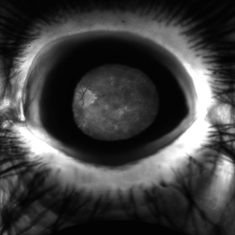

Birdshot: a View From the Outside

Birdshot: a View From the Outside

Nov 3 2019 by Julia Farah, MD

61-year-old female presented with classic birdshot chorioretinopathy.

Photographer: Peter Guingab

Imaging device: Optos California

Condition/keywords: birdshot choroidopathy, uveitis, white dot syndrome